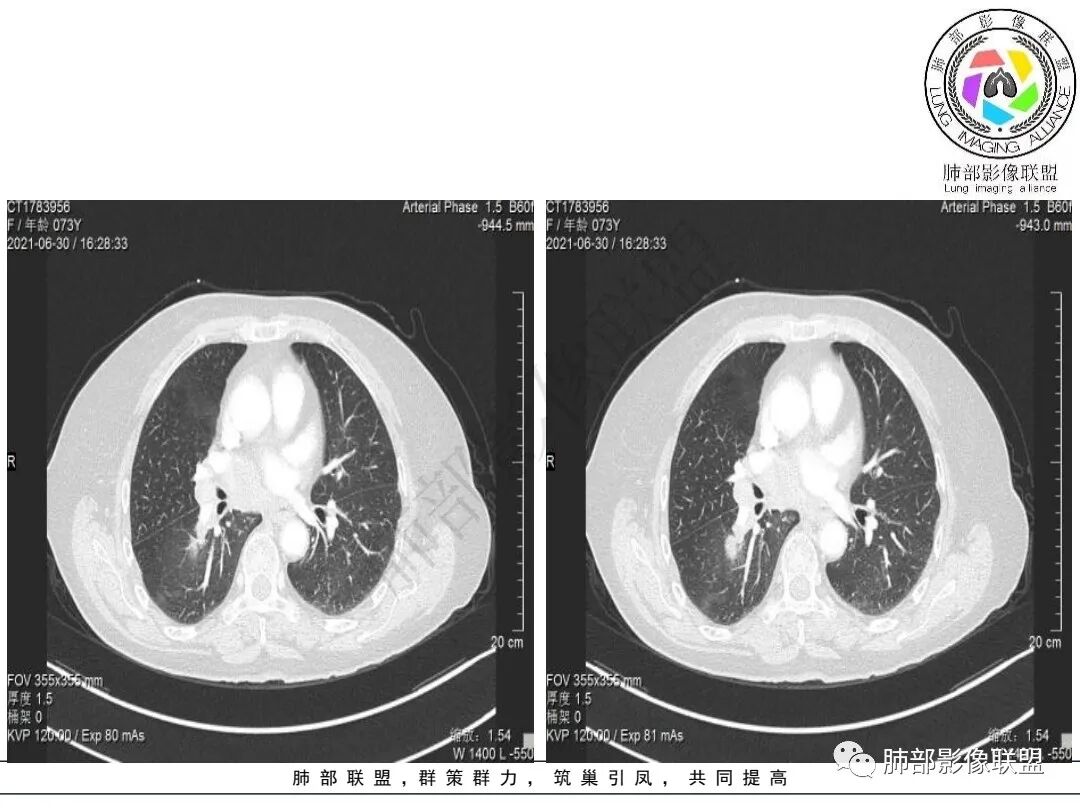

1.老年女性,咳嗽两月。CEA,T-spot阴性。

2.右肺下叶不规则实性密度块影,占据外后基底段及背段较大范围,可见轻度分叶、毛刺及棘状突起,未见明显胸膜牵拉及凹陷。

3.右肺下叶支气管轻度狭窄,病灶内见部分充气支气管征,外后基底段不能连续跟踪。

轻度不均匀强化,病灶内小血管显示不满意,未见明确坏死区。

4.右肺门及纵隔见多处增大淋巴结,不均匀环形强化,后下纵隔(隆突下)肿大淋巴结十分显眼!